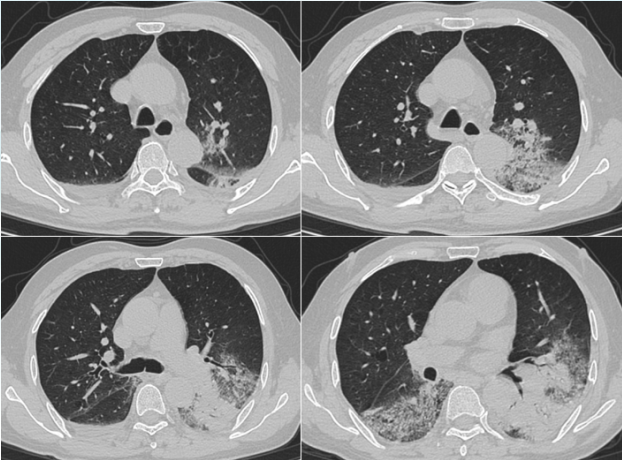

治疗后患者体温逐步恢复正常,炎症指标下降。复查胸部CT(2025-02-18)可见双肺炎症稍吸收(图3)

图片

3  患者治疗前后胸部CT对比

202535日复查胸部CT病灶较前进展(图4),炎症指标有所回弹,以中性粒细胞升高为主,抗感染方案调整为哌拉西林他唑巴坦4.5 g q9h+奥环素300 mg qd po

4  患者复查胸部CT对比

2025312日患者氧合无明显改善,复查胸部CT示肺部病灶进展(图4)将抗生素方案调整为美罗培南+米卡芬净+莫西沙星,甲泼尼龙抗炎,无创呼吸机辅助通气。

普通病房治疗期间出现如下问题:患者经鼻高流量无法脱机,且逐步加重202535日和312日先后两次复查胸部CT,肺部影像学进展明显患者咳痰乏力,自拔管后即发现右侧肢体肌力下降,病理征阴性,头颅CT无异常。经肺康复与功能康复锻炼后咳痰能力、右侧肌力仍恢复欠佳2025313日膈肌功能评估:膈肌厚度0.14~0.16 cm,增厚分数下降,膈肌移动度下降